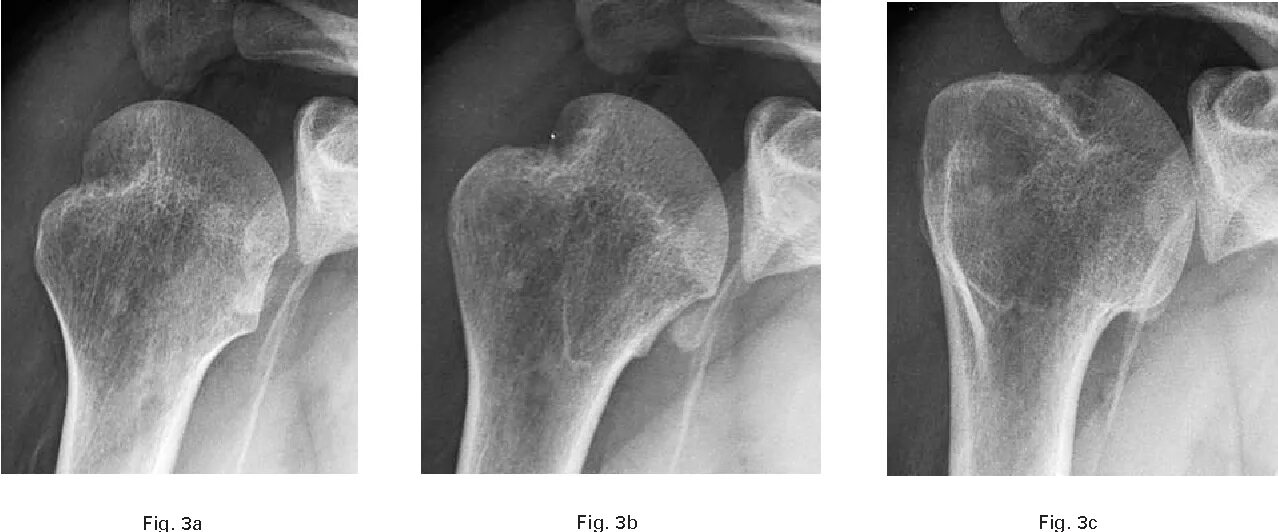

Pre operation